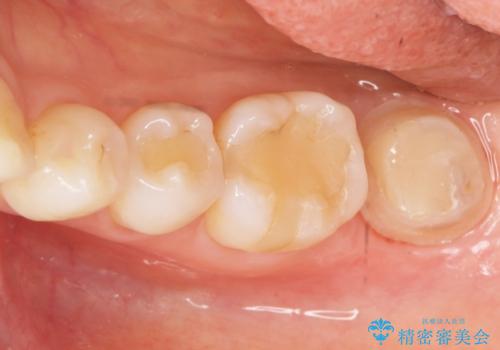

インプラントや義歯を用いることなく咬合を回復することができ、喜んで頂けました。

治療期間も抜歯後3ヶ月以内かつ少ない来院回数(初診含めて6回)で治療を終えることができ、ご満足頂けました。

被せ物の種類:メタルボンドクラウン エコノミー フルベイク